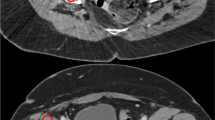

source and the trochanteric source (row d). Some air visible in the sources is due to incomplete filling of the tubes. Note the dark streak artefacts around the prosthesis, which largely disappear from the MAR corrected CT. White streak artefacts are mainly situated anterior and posterior to the prosthesis

PET and CT images from the phantom experiment. Results of the scam experiment are shown in the upper row. Further rows show the results of the prosthesis experiment. The two columns to the left are not corrected by MAR, those to the right are. Corresponding CT (left) and PET (right) images are given. The top two rows show coronal images; to indicate the position of the sources, which were not all in the same coronal plane, the PET images are composites of several slices. The lower rows show axial slices at the level of the lateral acetabular source (row a), the lateral neck source (row b), the medial acetabular source (row c), and the medial neck

That the predominant effect of MAR was to increase SUV in the areas surrounding the prostheses, does not contradict the possibility of overestimation of activity in particular areas around the prosthesis, such as have been reported clinically [5, 8, 11, 14]. However, overestimation seems confined to small regions and would typically only be picked up by small (10 to 15 mm diameter) regions of interest as used in [8, 11, 14] and specifically directed to bright streak artefacts. Both in our phantom experiment and in patients, bright streak artefacts indeed did occur, but were mainly oriented in the anteroposterior direction (Figs. 2, 12 and 13). In the larger midplane regions that we used, these would not be expected to affect our measurements to a large extent, and overestimation it is prevailed upon by underestimation.